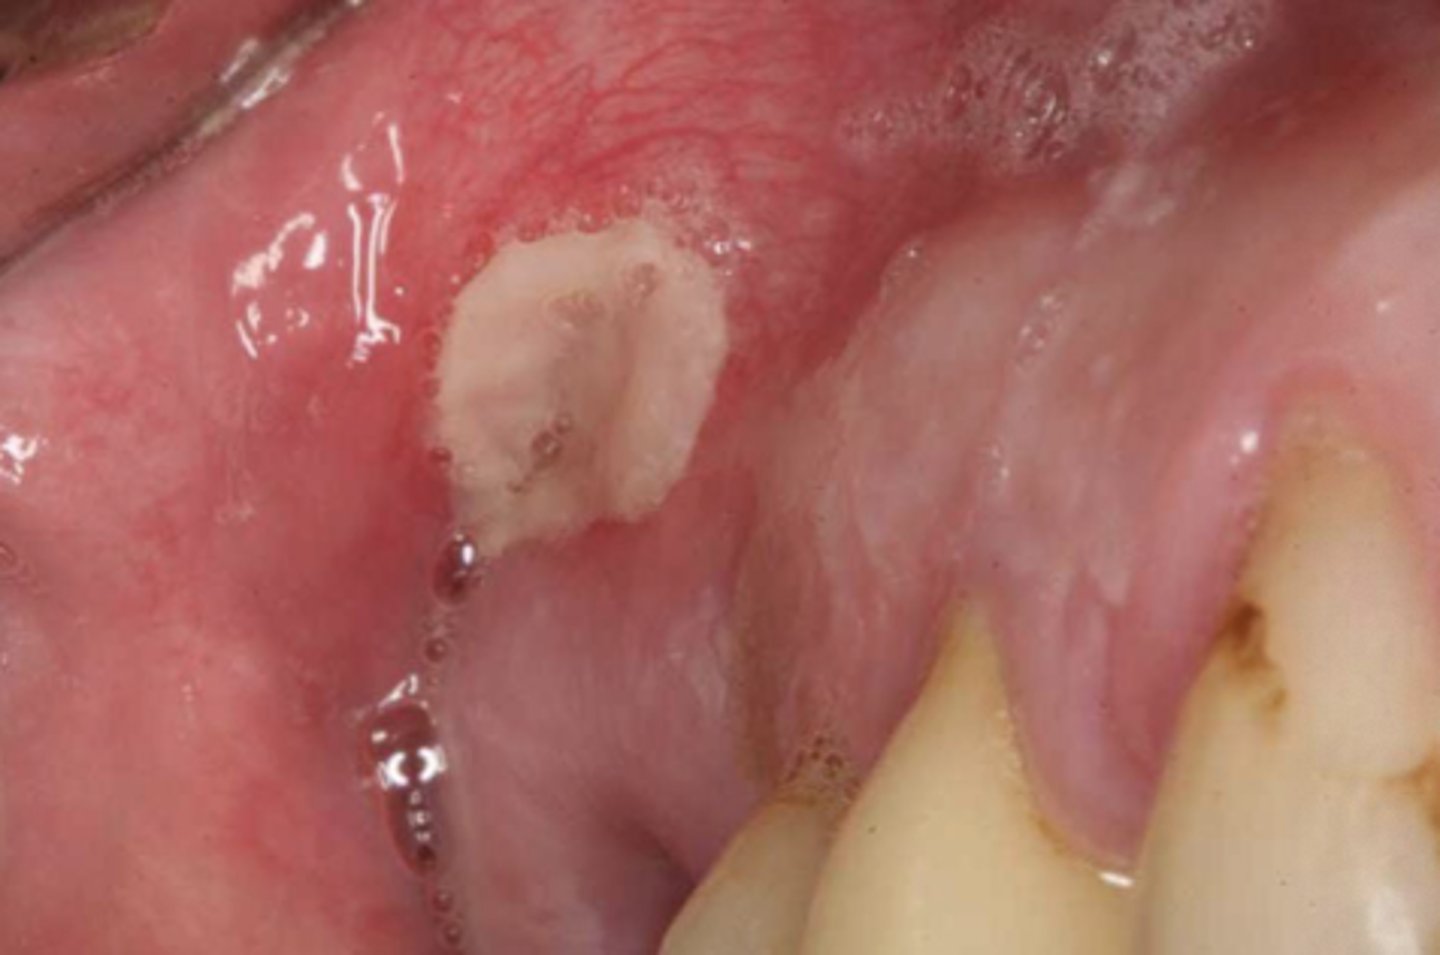

Which condition is associated with topical tobacco use?

Verrucous carcinoma

- Nicknamed "snuff dippers cancer"

T/F: Verrucous carcinoma is considered a high grade variant of SCC

False - low grade variant of SCC

T/F: Verrucous carcinoma is fast growing

False - slow growing

How does verrucuous carcinoma invade?

Invades as a "moving front"

- has not breached basement membrane yet

- very slow pattern of invasion

Verrucous carcinoma in an edentulous pt

- txt?

White, warty leukoplakia with thickened areas

- Txt: Serial biopsies over time, can use CO2 laser